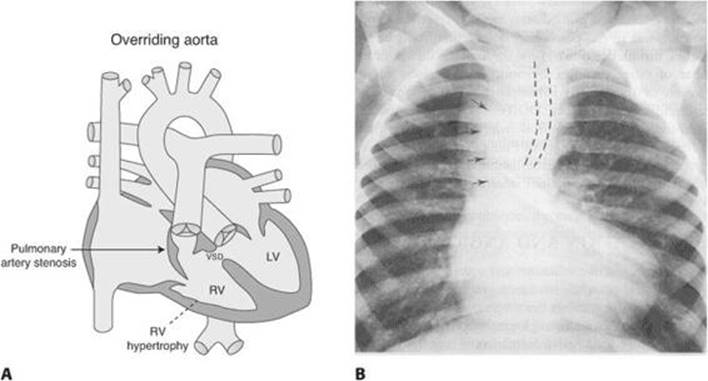

CXR (Figure 13-3).

“Boot-shaped heart.”

↓ pulmonary vascular markings.

Right aortic arch (25%).

FIGURE 13-3. Chest x-ray in tetralogy of Fallot.

Arrows indicate right-sided aortic arch and upper thoracic aorta. Dashed lines indicate right-sided aortic indentation on the air bronchogram. (Reproduced, with permission, from Rudolph CD, et al (eds). Rudolph’s Pediatrics, 21st ed. New York: McGraw-Hill, 2002: 1821.)